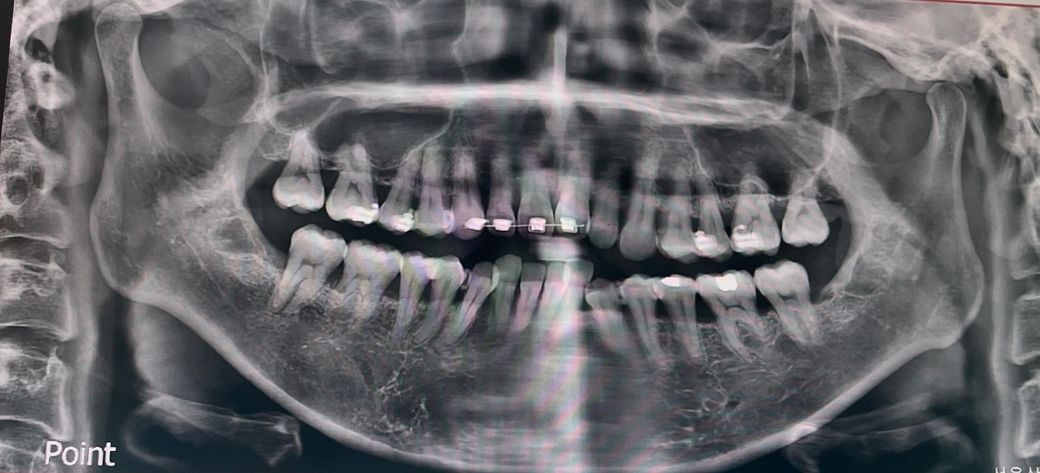

엑스레이 전체적인 치아상태 좀 봐주세용

교정진행중이라 일부만 달고 나머지는 곧 다는데요

잇몸이안좋아보이는데 교정하기 괜찮은가요 전체적인상태가 어때보이시나요?

30대후반입니다

잇몸뼈의 상태나 치아 뿌리의 상태 등이 아주 건강한 편은 아닙니다. 교정치료는 가능합니다.

치아 뿌리들이 짧고 30대에 교정을 한다면 잇몸이 안좋아질 가능성이 높으니 관리를 철저히 하시는게 좋을것같습니다.

브라켓이 부착되어 있는 파노라마 사진으로는 교정상태나 치아 상태를 정확하게 확인하기 어렵습니다.

나이에 비해 잇몸뼈 높이가 낮은편입니다. 잇몸과 잇몸뼈는 한번 낮아지면 재생이 어렵고, 교정으로 인해 퇴축이 가속화될 수 있습니다

교정 전 잇몸관련하여 치주과 의사와도 상담받아보세요